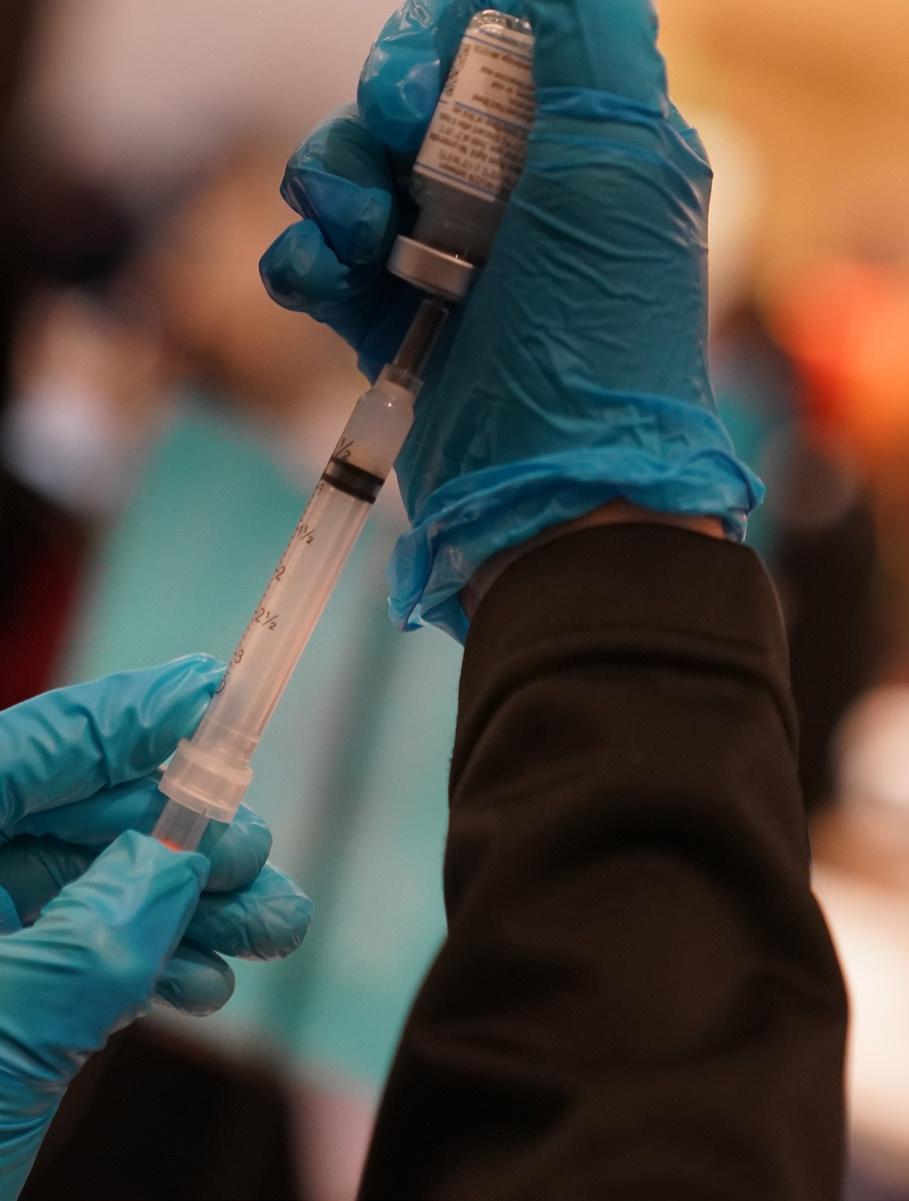

making a difference one vaccine at a time

To our fearless nurses, first responders, volunteers and registration teams: we thank you for your bravery, dedication and hard work. Thanks to you, the City of Mission, in partnership with Hidalgo County, Precinct 3 Commissioner Everardo “Ever” Villarreal, Sharyland ISD, and Mission CISD, has successfully vaccinated hundreds of people. It’s all in an effort to keep our community safe!

Throughout this pandemic, the City of Mission has been focused on protecting our community. We’re proud to protect and serve our All-America City during this challenging time. Mission health officials are working to get more people vaccinated as quickly as possible. Stay tuned for more community COVID-19 vaccination clinics headed to our city!